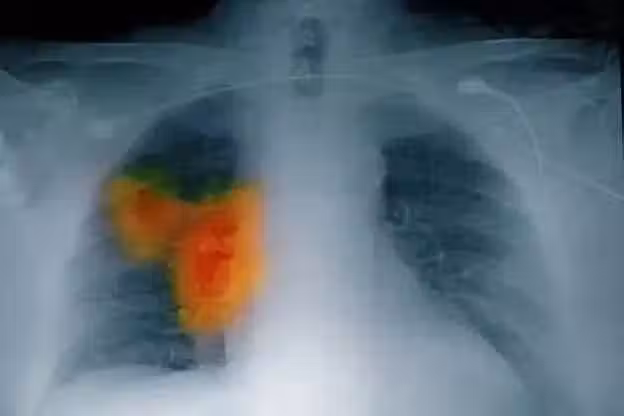

58歲婦女確診肺癌,強忍淚水坦言:手部早出現了問題,沒有多重視

在這裡得跟大家說個關鍵的事兒,很多人都沒意識到,手部的一些小變化,就像藏在身體里的 「小警報」,可能和其他重要器官的疾病緊密相連。

比如說,手部要是一直麻麻的、沒力氣,或者時不時輕微地抖兩下,這很可能是神經系統或者血液循環系統出問題的信號。

在糖尿病、心臟病這些慢性病患者身上,這種情況就很常見。

而在李阿姨的身上,手部的這些問題,居然成了早期肺癌的一個危險信號。